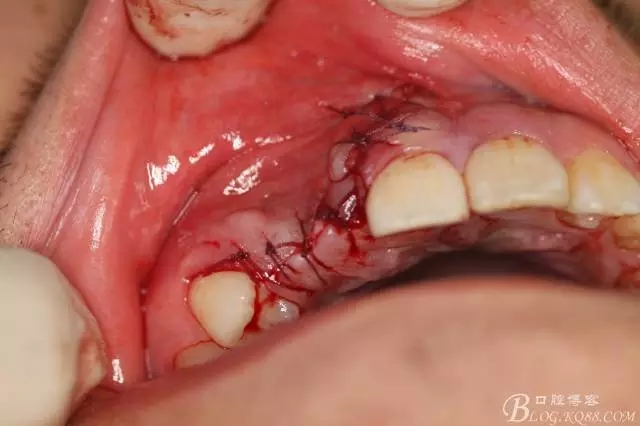

圖14.摘除牙瘤后形成的巨大骨缺損。

圖15.牙瘤摘除后暴露出13、12部分牙冠。

圖17.縫合創(chuàng)口。12、13觀察,一年后復(fù)查。